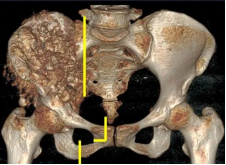

术前影像

日前,安医大一附院骨病骨肿瘤外科胡勇教授团队成功完成一例复杂骨盆Ⅰ+Ⅱ+Ⅲ+Ⅳ区肿瘤切除与3D打印组配式半骨盆假体重建手术。患者为女性,53岁,下腰痛半年余,右侧臀部膨隆,右侧下肢轻度浮肿。右侧髂棘髂窝及臀部可触及巨大肿物,压痛明显,右髋外展前屈活动受限,右侧大腿感觉麻木,右足感觉运动正常。骨盆肿瘤切除重建是骨科专业中难度极大、风险极高的手术。骨盆肿瘤约占原发骨肿瘤的3%~4%,其中以软骨系统肿瘤最为多见,其次为骨巨细胞瘤、成骨肉瘤等,儿童尤文肉瘤亦好发于骨盆。

据主刀医师徐生林介绍,本例病例将整个右侧半骨盆Ⅰ+Ⅱ+Ⅲ+Ⅳ区(累及骶骨)进行整块切除,同时切除肿瘤覆盖的部分骶骨。3D打印假体所有骨接触界面均设计为骨整合结构,有利于骨长入和骨盆假体的永久稳定。耻、坐骨结构不规则,因此设计组配式结构,有利于术中操作,极大地方便了术中的假体安装。